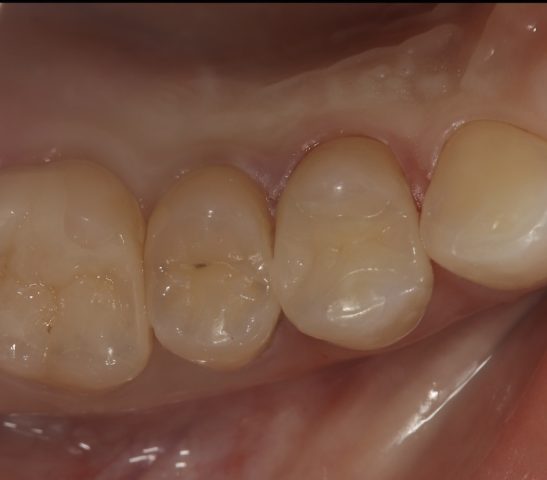

| 診断名 | セラミックインレーの審美補綴治療 |

|---|---|

| 年齢・性別 | 20代・女性 |

| 治療期間・回数 | 2週間~3週間/2回 |

| 治療方法 | セラミックインレーによる審美補綴治療 |

| 費用 | 55,000円(税込み) |

| デメリット・注意点 | 保険が適用できないため自費診療になる。 セラミックスインレー・クラウンに強い力がかかると割れてしまう恐れがあるため、歯ぎしりや食いしばりが癖になっている患者様にはおすすめできない場合がある。 |